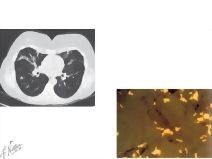

Nontuberculous Mycobacterial Lung Disease